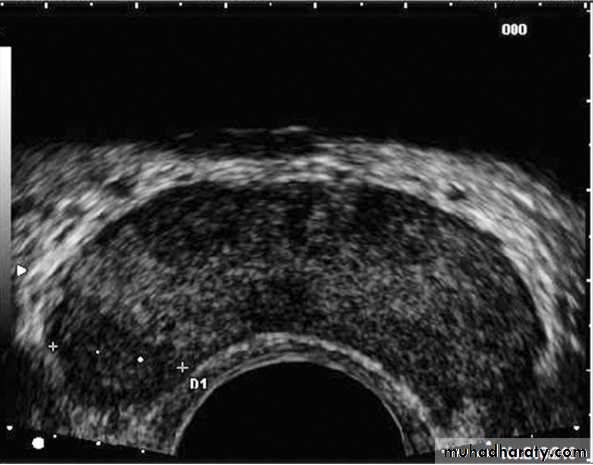

1. TRUS (transrectal ultrasound):

is useful in performing prostatic biopsies and in providing local staging information if cancer is detected.

Almost all prostate needle biopsies are performed under TRUS guidance. This makes lesion-directed biopsies possible.

If visible, CaP tends to appear as a hypoechoic lesion in the peripheral zone.